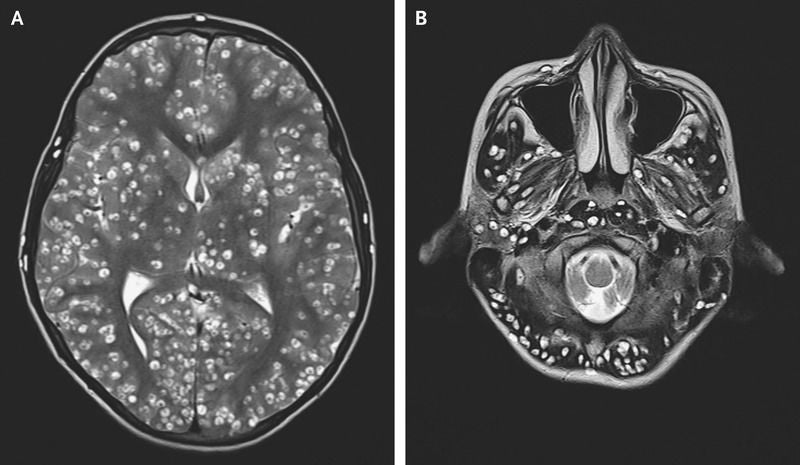

Acude al hospital con dolor de cabeza y le encuentran una plaga de gusanos en el cerebro

Ocurrió en un hospital de Faridabad, India. Un joven de 18 años llega aquejado de fuertes dolores en la cabeza y convulsiones, desorientado y con el lado derecho de la ingle afectada durante una semana. Una resonancia magnética revela la causa: una plaga de tenias parasitarias de cerdo, la Taenia solidum.